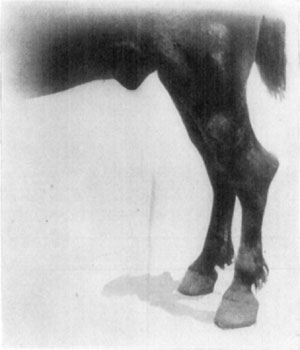

A sequel of chronic lymphangitis is a condition known as elephantiasis. In such cases there occurs a hyperplasia of the skin and subcutaneous tissues, resulting in some instances, in the affected member attaining an enormous size. Sporadic cases of this kind are to be seen occasionally, and are apparently caused by repeated attacks of lymphangitis. The affection is not benefited by treatment, and while a horse's leg may become so heavy and cumbersome as to mechanically impede its gait, as well as to fatigue the subject when made to do service even at a slow pace, elephantiasis causes no constitutional derangement. The hind legs, in elephantiasis, are affected and a unilateral involvement is more often seen than a bilateral one. The legs may be enlarged from the extremity to the body, but ordinarily the affection does not extend higher than the hock or the mid-tibial region.